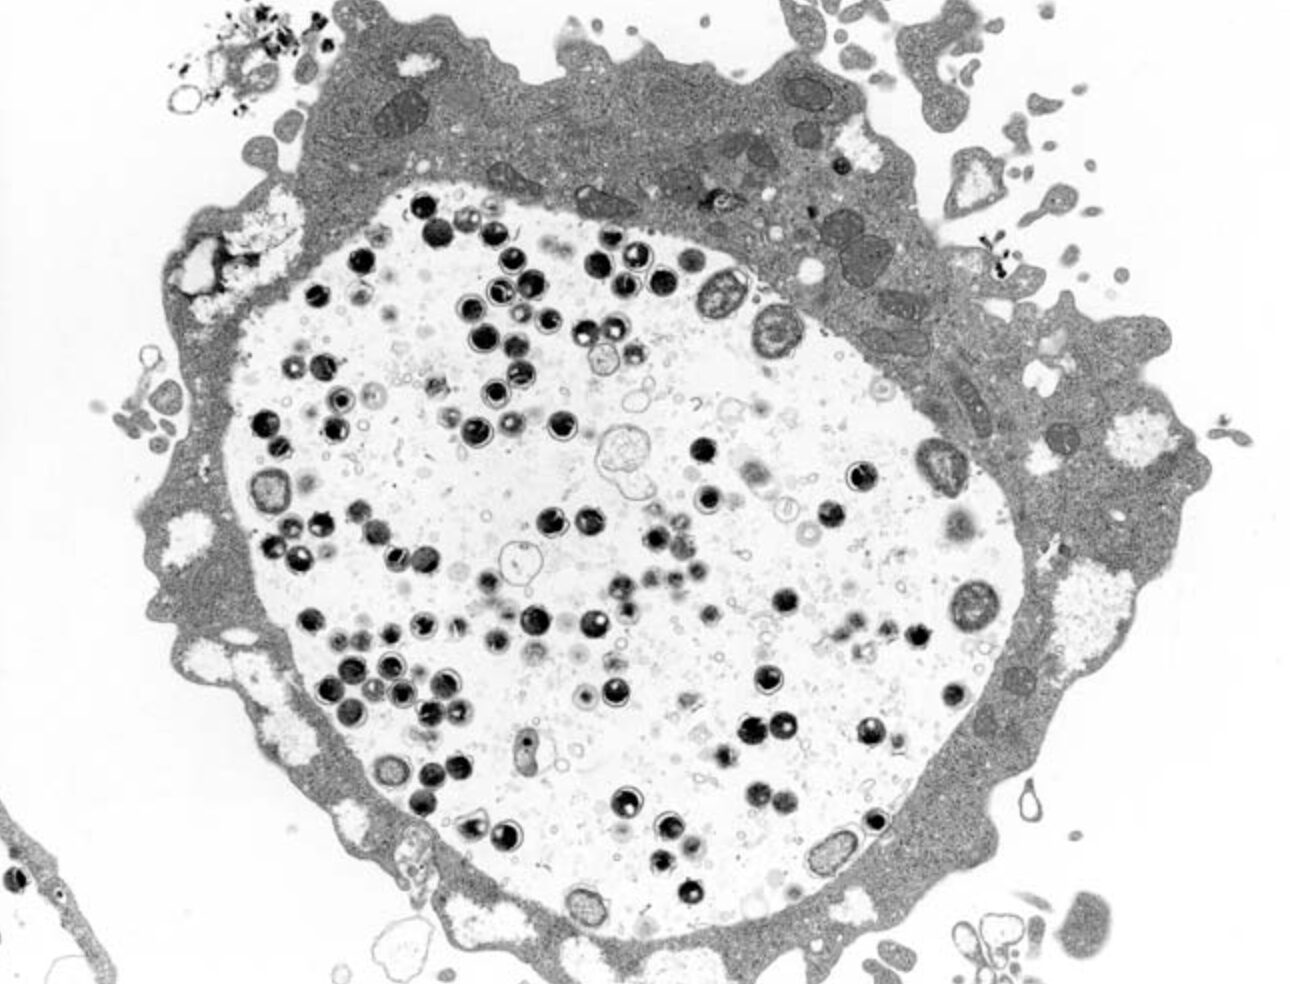

クラミジアとは?

クラミジアとは、細菌クラミジア・トラコマティスに感染して発症する性感染症です。